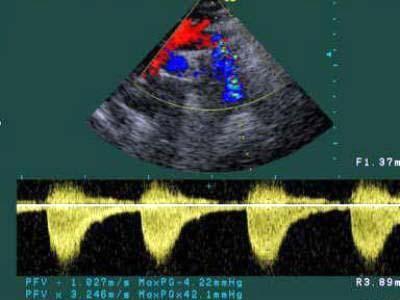

问题 患者,男,8岁,因腹痛伴呕吐1个月,持续加重1周入院,行心脏及腹部超声检查,下图为胸骨上窝大动脉长轴切面,根据图像显示,该患者最有可能诊断为?(?)

选项 A.动脉导管未闭 B.主-肺动脉间隔缺损 C.主动脉缩窄 D.肺动脉狭窄 E.室间隔缺损

答案 C